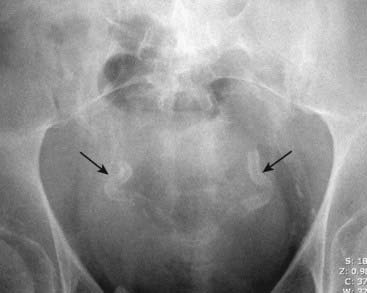

image

Figure 16-5 Calcification of the vas deferens.

This patient manifests two tracklike calcifications (solid black arrows) symmetrically on each side of the urinary bladder that end in the urethra in this man who also has an enlarged prostate which is elevating the base of the bladder. This type of calcification identifies it as occurring in the wall of a tubular structure. The location identifies it as calcification in the walls of the vas deferens, which occurs more commonly and earlier in diabetics than as a natural degenerative process.